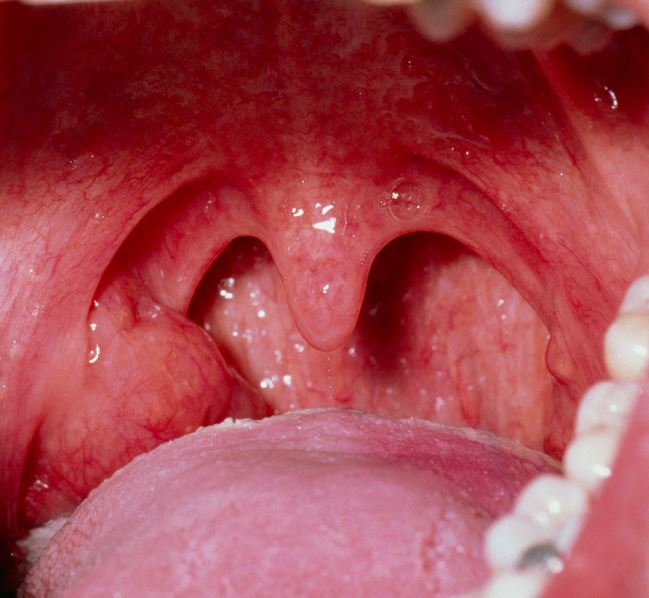

Eine unilateral vergrößerte Gaumenmandel weckt den Verdacht auf eine bösartige Erkrankung. Bei asymptomatischen Betroffenen könnte eine diagnostische Tonsillektomie aber unnötig sein, wie eine Studie aus England zeigt.

© Dr. P. Marazzi / Science Photo Library